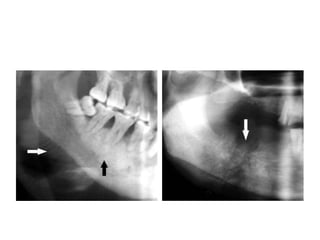

Mixed form of ostiosarcoma: In addition to areas of

observed. Note the areas of spicules

(arrows)